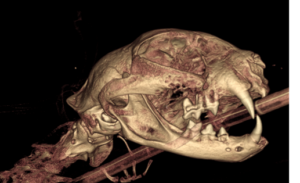

3D reconstruction of a cat with an oral tumor causing severe bone loss